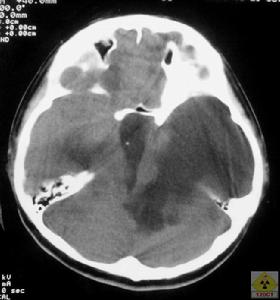

4、頭顱CT或MRI可以顯示雙側腦室對稱性擴大第三腦室及第四腦室也擴大腦萎縮連續顱內壓監護可發現患者熟睡後的眼動期出現顱內壓升高現象據此可與腦萎縮引起的老年性痴呆相鑑別腰椎穿刺示腦脊液壓力正常,CSF檢查正常

1.影像學檢查頭顱CT檢查是正常顱壓腦積水檢查重要手段,它可確定腦室擴大和皮質萎縮的程度及引起腦積水的病因,同時,也是觀察術後分流效果及併發症的手段。典型的CT掃描表現為腦室擴大而皮質萎縮不明顯。MRI影像可從矢、冠、水平全方位觀察較小的顱內病變並優於CT,同時通過MRI可觀察腦脊液的動力學變化,對腦積水進行評價。腦室周圍T1加權像低信號改變可表明腦積水呈進展趨勢。

頭顱CT掃描3、分流失敗分析:對正常顱壓腦積水選擇合適壓力的分流管至關重要,只有分流後使腦壓儘可能降低才能達到腦室縮小、症狀改善的效果。但腦壓下降過度則會引起術後一些合併症: